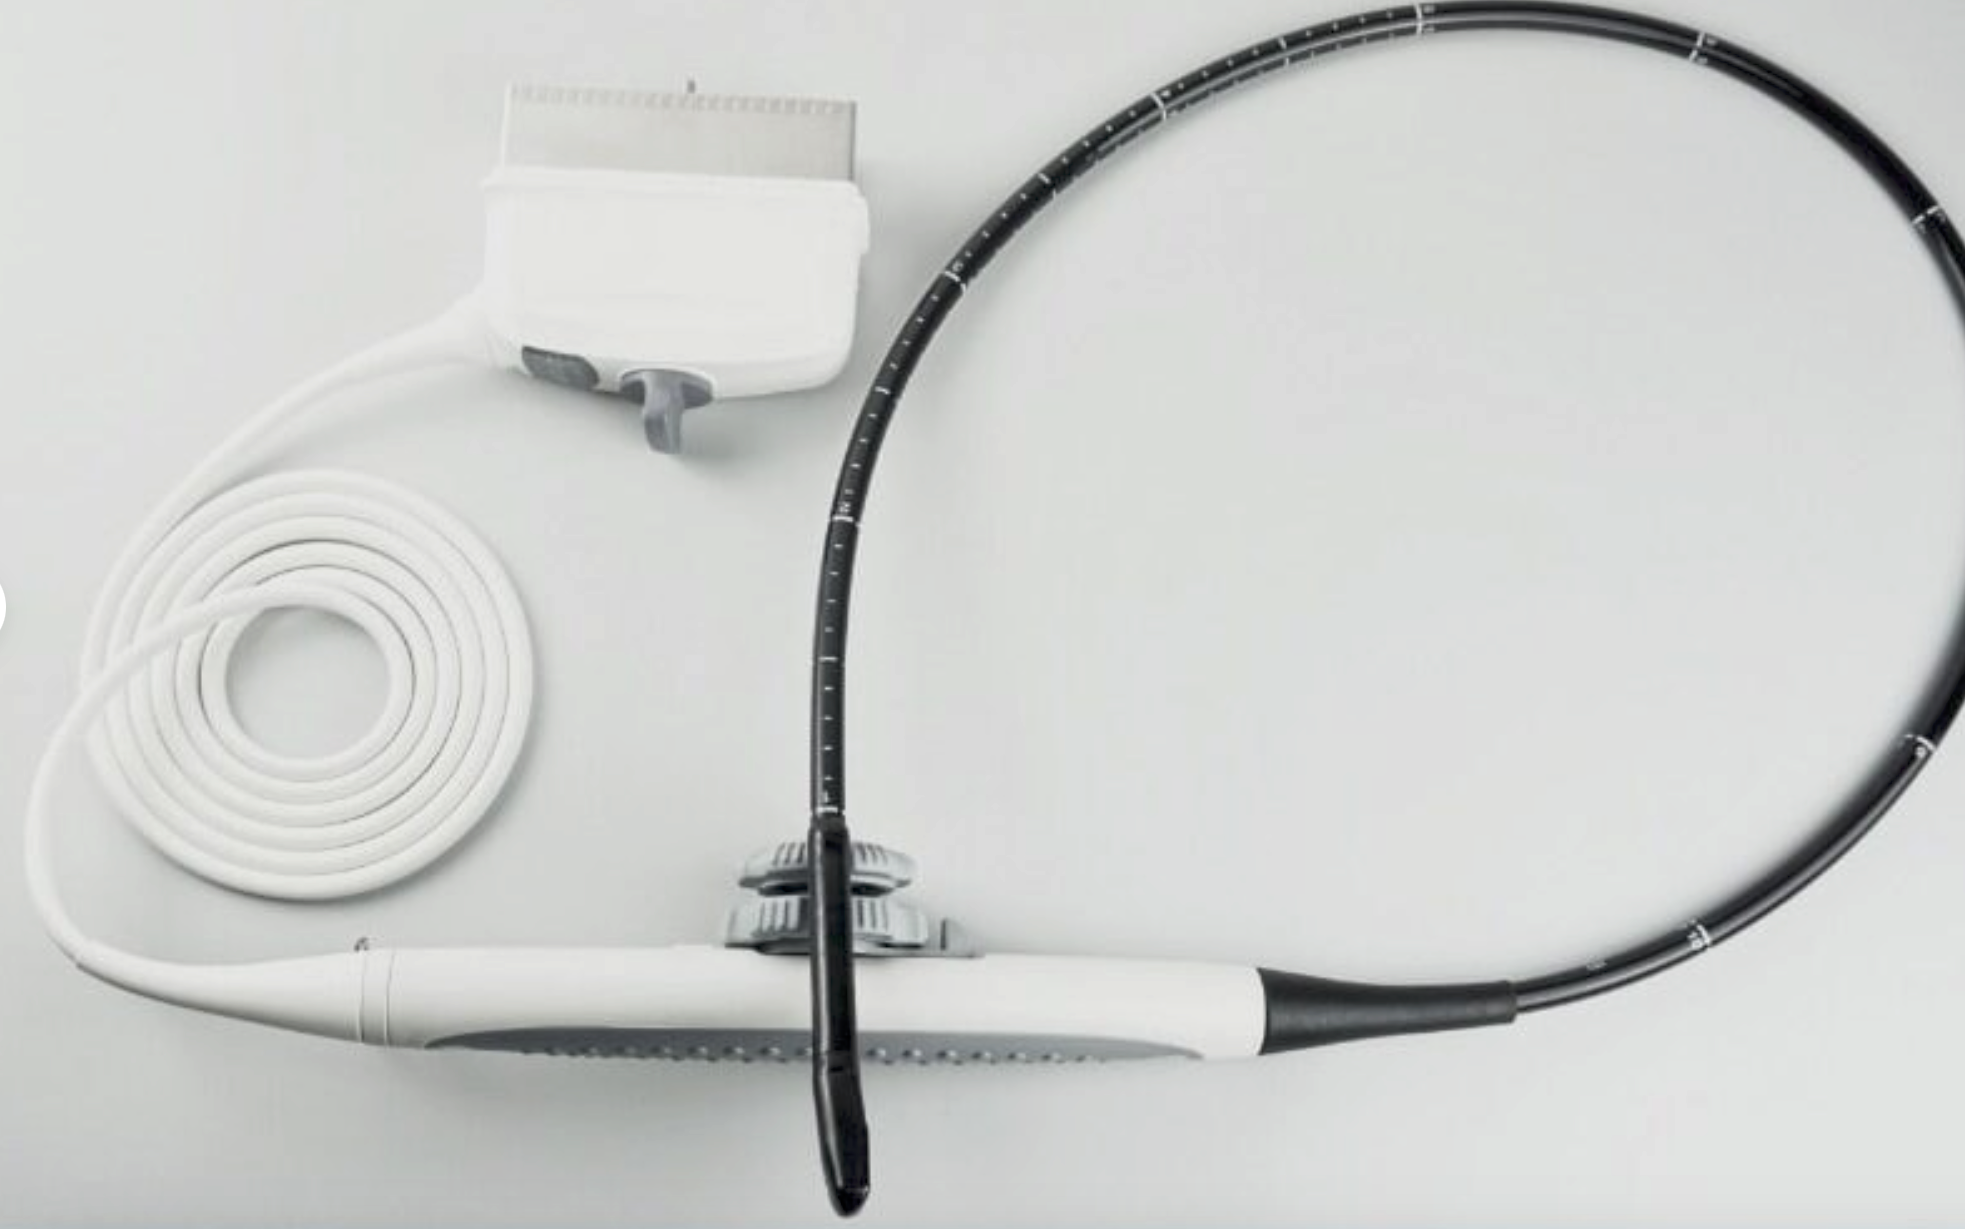

Explore the dependable and sophisticated GE Portable Logiq Book Ultrasound equipped with E8C-RS OB/GYN and 3C-RS Abdominal Transducers. Condition: Gently used with signs of cosmetic wear, yet remains fully operational for accurate diagnostics. Ideal for medical professionals seeking precision with a well-maintained machine. Brand: GE, Model: LOGIQ BOOK. Click to view our detailed listing and invest in advanced medical technology.